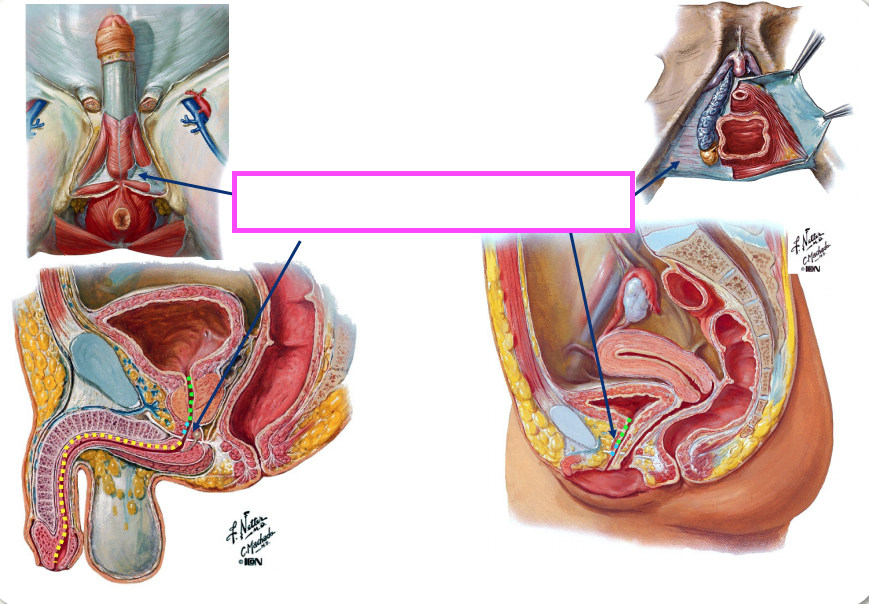

Main Sites of Constriction in the Ureter

The lumen of the ureter is susceptible to constriction at 3 main sites, which are therefore prone to obstruction by renal calculi (stones):

Ureter in the Female

In the female, the ureters are crossed superiorly by the uterine arteries lateral to the cervix, and they are vulnerable to injury at this location during hysterectomy.

Male Urethra

•The male urethra has three parts:

Uretovesicle Junction

The bladder wall forms a flap valve at the ureterovesicle junction.

Membranous urethra (location of voluntary sphincter)